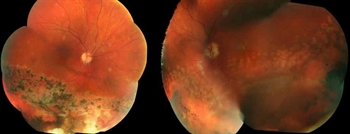

The patient presented with new worsening vision in both eyes. Around one month prior to presentation, he was switched to immunotherapy with ipilimumab, nivolumab, and cabozantinib. Visual acuity measured count fingers in both eyes from a previous 20/80 in the right eye (OD) and 20/200 in the left eye (OS). Intraocular pressure, pupillary exam, and confrontational visual fields were normal. Anterior segment examination was overall unremarkable with clear corneas and trace nuclear sclerotic cataracts bilaterally. Dilated fundoscopic exam showed new mild bilateral vitritis and stable bilateral choroidal lesions with overlying pigmentary changes (Figure 1). Greater subretinal fluid was present in the macula than previously observed. Optical coherence tomography confirmed increased subretinal fluid and revealed a subretinal fibrinoid response (Figure 2).

Figure 1. Color fundus photos showing bilateral choroidal lesions with overlying pigment changes. |

Figure 2. Spectral-domain optical coherence tomography (SD-OCT) demonstrating intraretinal fluid, and subretinal fluid with subretinal fibrinoid response bilaterally. |